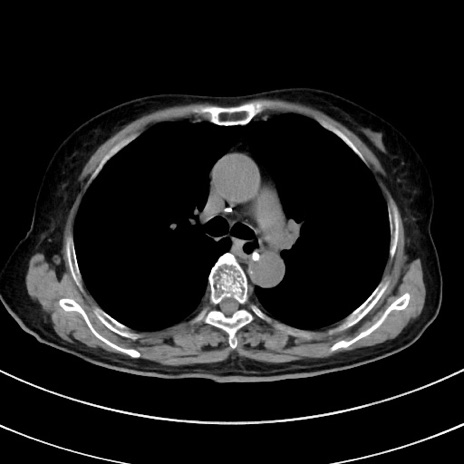

症例33(横断像)

【症例】70歳代 女性

【主訴】心窩部痛

【現病歴】延髄病変の精査・加療にて神経内科入院中。本日より心窩部痛あり。

【身体所見】右下腹部を中心に圧痛と反跳痛あり。

【データ】WBC 10900、CRP 0.02